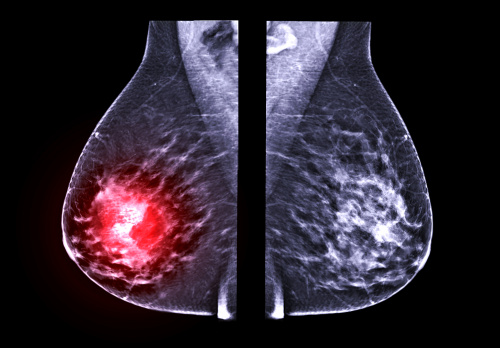

Диагностические мероприятия часто начинаются с самообследования. Во время самоосмотра женщине, заметившей у себя подозрительные выделения или уплотнение, необходимо обратиться к маммологу.

После опроса проводится осмотр: оценивается состояние кожных покровов, слизистых оболочек, выполняется поверхностная, затем глубокая пальпация молочных желез. Также пальпируются лимфоузлы, прилегающие к груди.

Лабораторное и инструментальное обследование включает в себя:

Существуют клиническое и патоморфологическое стадирование заболевания. Первый вариант классификации осуществляется на основании клинических методов исследования. Данные анализа биоптата позволяют провести патоморфологическое стадирование.

Онкологи в своей практике используют TNM-классификатор, где Т – характеристика первичного образования, N – прилегающие лимфоузлы, М – отдаленные метастатические очаги.